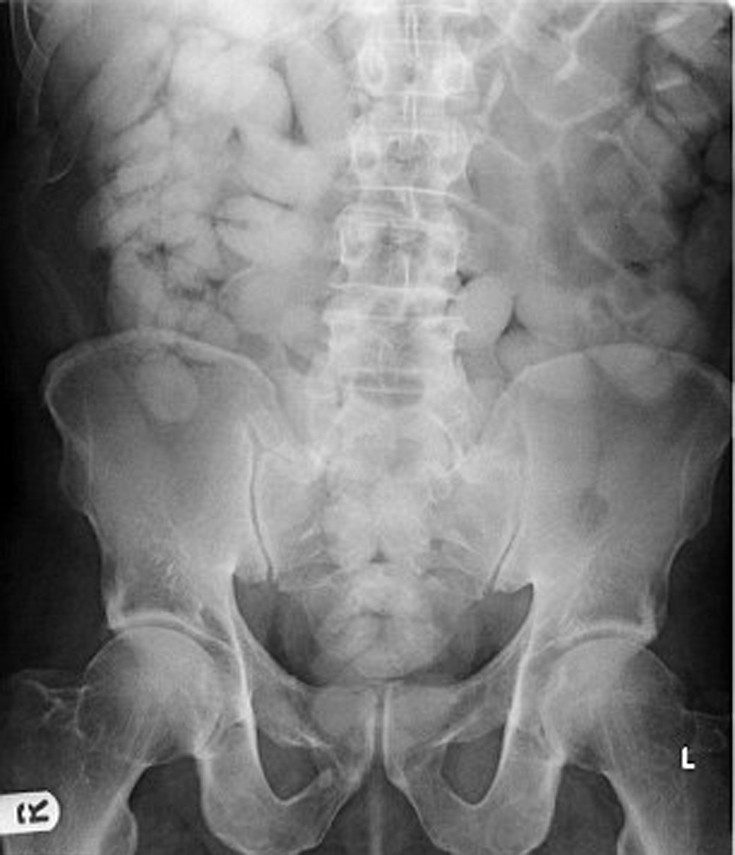

Είναι μια φωτογραφία από… ακτινογραφία ενός άνδρα που συνελήφθη στα σύνορα της Βρετανίας και απεικονίζει τα πακετάκια με ναρκωτικά που ο άνδρας είχε καταπιεί, ναρκωτικά αξίας δεκάδων χιλιάδων ευρώ!

Τα εν λόγω βαποράκια ρισκάρουν τη ζωή τους καταπίνοντας ακόμα και 120 μικρά δέματα με ναρκωτικά τυλιγμένα σε… προφυλακτικά, μπαλόνια ή διάφανη μεμβράνη.

Εάν ένα από τα δεματάκια, που περιέχουν ηρωίνη ή κοκαΐνη, σκάσει, ο άνθρωπος που τα έχει καταπιεί κινδυνεύει ακόμα και να πεθάνει εκτός κι αν λάβει άμεσα ιατρική βοήθεια.